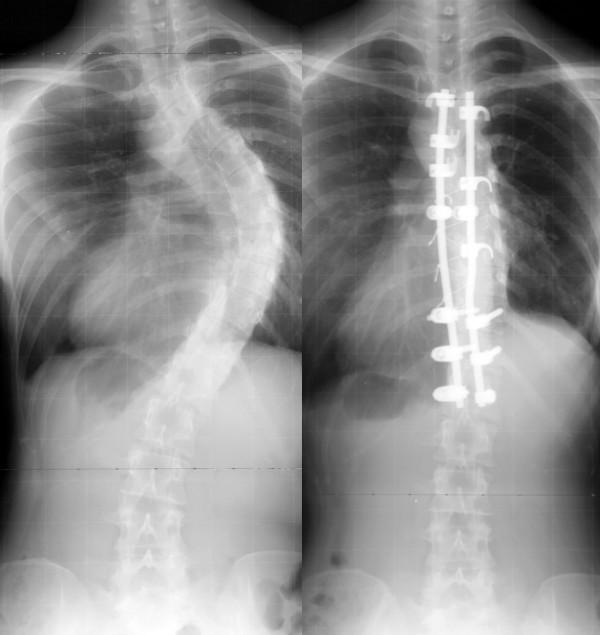

In this review, basic knowledge and recent innovation of surgical treatment for scoliosis will be described. Surgical treatment for scoliosis is indicated, in general, for the curve exceeding 45 or 50 degrees by the Cobb's method on the ground that:1) Curves larger than 50 degrees progress even after skeletal maturity.2) Curves of greater magnitude cause loss of pulmonary function, and much larger curves cause respiratory failure.3) Larger the curve progress, more difficult to treat with surgery.Posterior fusion with instrumentation has been a standard of the surgical treatment for scoliosis. In modern instrumentation systems, more anchors are used to connect the rod and the spine, resulting in better correction and less frequent implant failures. Segmental pedicle screw constructs or hybrid constructs using pedicle screws, hooks, and wires are the trend of today.Anterior instrumentation surgery had been a choice of treatment for the thoracolumbar and lumbar scoliosis because better correction can be obtained with shorter fusion levels. Recently, superiority of anterior surgery for the thoracolumbar and lumbar scoliosis has been lost. Initial enthusiasm for anterior instrumentation for the thoracic curve using video assisted thoracoscopic surgery technique has faded out.Various attempts are being made with use of fusionless surgery. To control growth, epiphysiodesis on the convex side of the deformity with or without instrumentation is a technique to provide gradual progressive correction and to arrest the deterioration of the curves. To avoid fusion for skeletally immature children with spinal cord injury or myelodysplasia, vertebral wedge ostetomies are performed for the treatment of progressive paralytic scoliosis. For right thoracic curve with idiopathic scoliosis, multiple vertebral wedge osteotomies without fusion are performed. To provide correction and maintain it during the growing years while allowing spinal growth for early onset scoliosis, technique of instrumentation without fusion or with limited fusion using dual rod instrumentation has been developed. To increase the volume of the thorax in thoracic insufficiency syndrome associated with fused ribs and congenital scoliosis, vertical expandable prosthetic titanium ribs has been developed.

在本综述中,将描述脊柱侧弯手术治疗的基础知识和最新创新。一般而言,脊柱侧弯的手术治疗适用于Cobb法测量角度超过45或50度的侧弯,原因如下:1)大于50度的侧弯即使在骨骼成熟后仍会进展。2)较大度数的侧弯会导致肺功能丧失,度数更大的侧弯会导致呼吸衰竭。3)侧弯进展越大,手术治疗越困难。后路融合内固定一直是脊柱侧弯手术治疗的标准方法。在现代内固定系统中,更多的锚钉用于连接棒与脊柱,从而实现更好的矫正效果,且植入物失败的频率更低。节段性椎弓根螺钉结构或使用椎弓根螺钉、钩和钢丝的混合结构是当今的发展趋势。前路内固定手术曾是胸腰段和腰段脊柱侧弯的一种治疗选择,因为它能在较短的融合节段下获得更好的矫正效果。最近,前路手术治疗胸腰段和腰段脊柱侧弯的优势已不复存在。最初对使用电视辅助胸腔镜手术技术进行胸椎侧弯前路内固定的热情已经消退。人们正在尝试各种非融合手术。为了控制生长,在畸形凸侧进行骨骺阻滞术(有无内固定)是一种提供渐进性矫正并阻止侧弯恶化的技术。对于脊髓损伤或脊髓发育不良的骨骼未成熟儿童,为避免融合,可进行椎体楔形截骨术来治疗进行性麻痹性脊柱侧弯。对于特发性脊柱侧弯的右胸弯,可进行多节段无融合椎体楔形截骨术。为了在生长期间提供矫正并维持矫正效果,同时允许早发性脊柱侧弯的脊柱生长,已开发出无融合或有限融合的双棒内固定技术。为了增加与融合肋骨和先天性脊柱侧弯相关的胸廓不全综合征患者的胸廓容积,已开发出垂直可扩张人工钛肋骨。